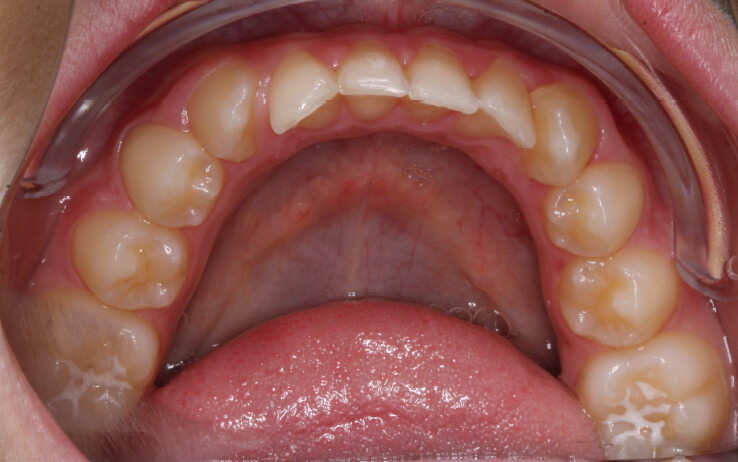

A 13-year-old male patient presented with a deep bite, characterized by near-complete coverage of the mandibular incisors. Clinical evaluation revealed bi-arch crowding, dental rotations, and proclination of the maxillary lateral incisors, contributing to the patient’s esthetic concerns. The facial profile was retrusive, consistent with mandibular retrognathism, and no significant periodontal abnormalities were detected.

The patient presented with a skeletal Class II relationship with bilateral molar and canine Class II and a Class II division 2 dental pattern. The deep bite was associated with anteroinferior crowding and an accentuated Curve of Spee. Facial analysis revealed good symmetry, a slightly increased lower facial third, and a convex profile characterized by mandibular and chin retrusion. Lip competence was mildly reduced, with a decreased nasolabial angle and mentalis hyperactivity, all of which compromised overall facial harmony.